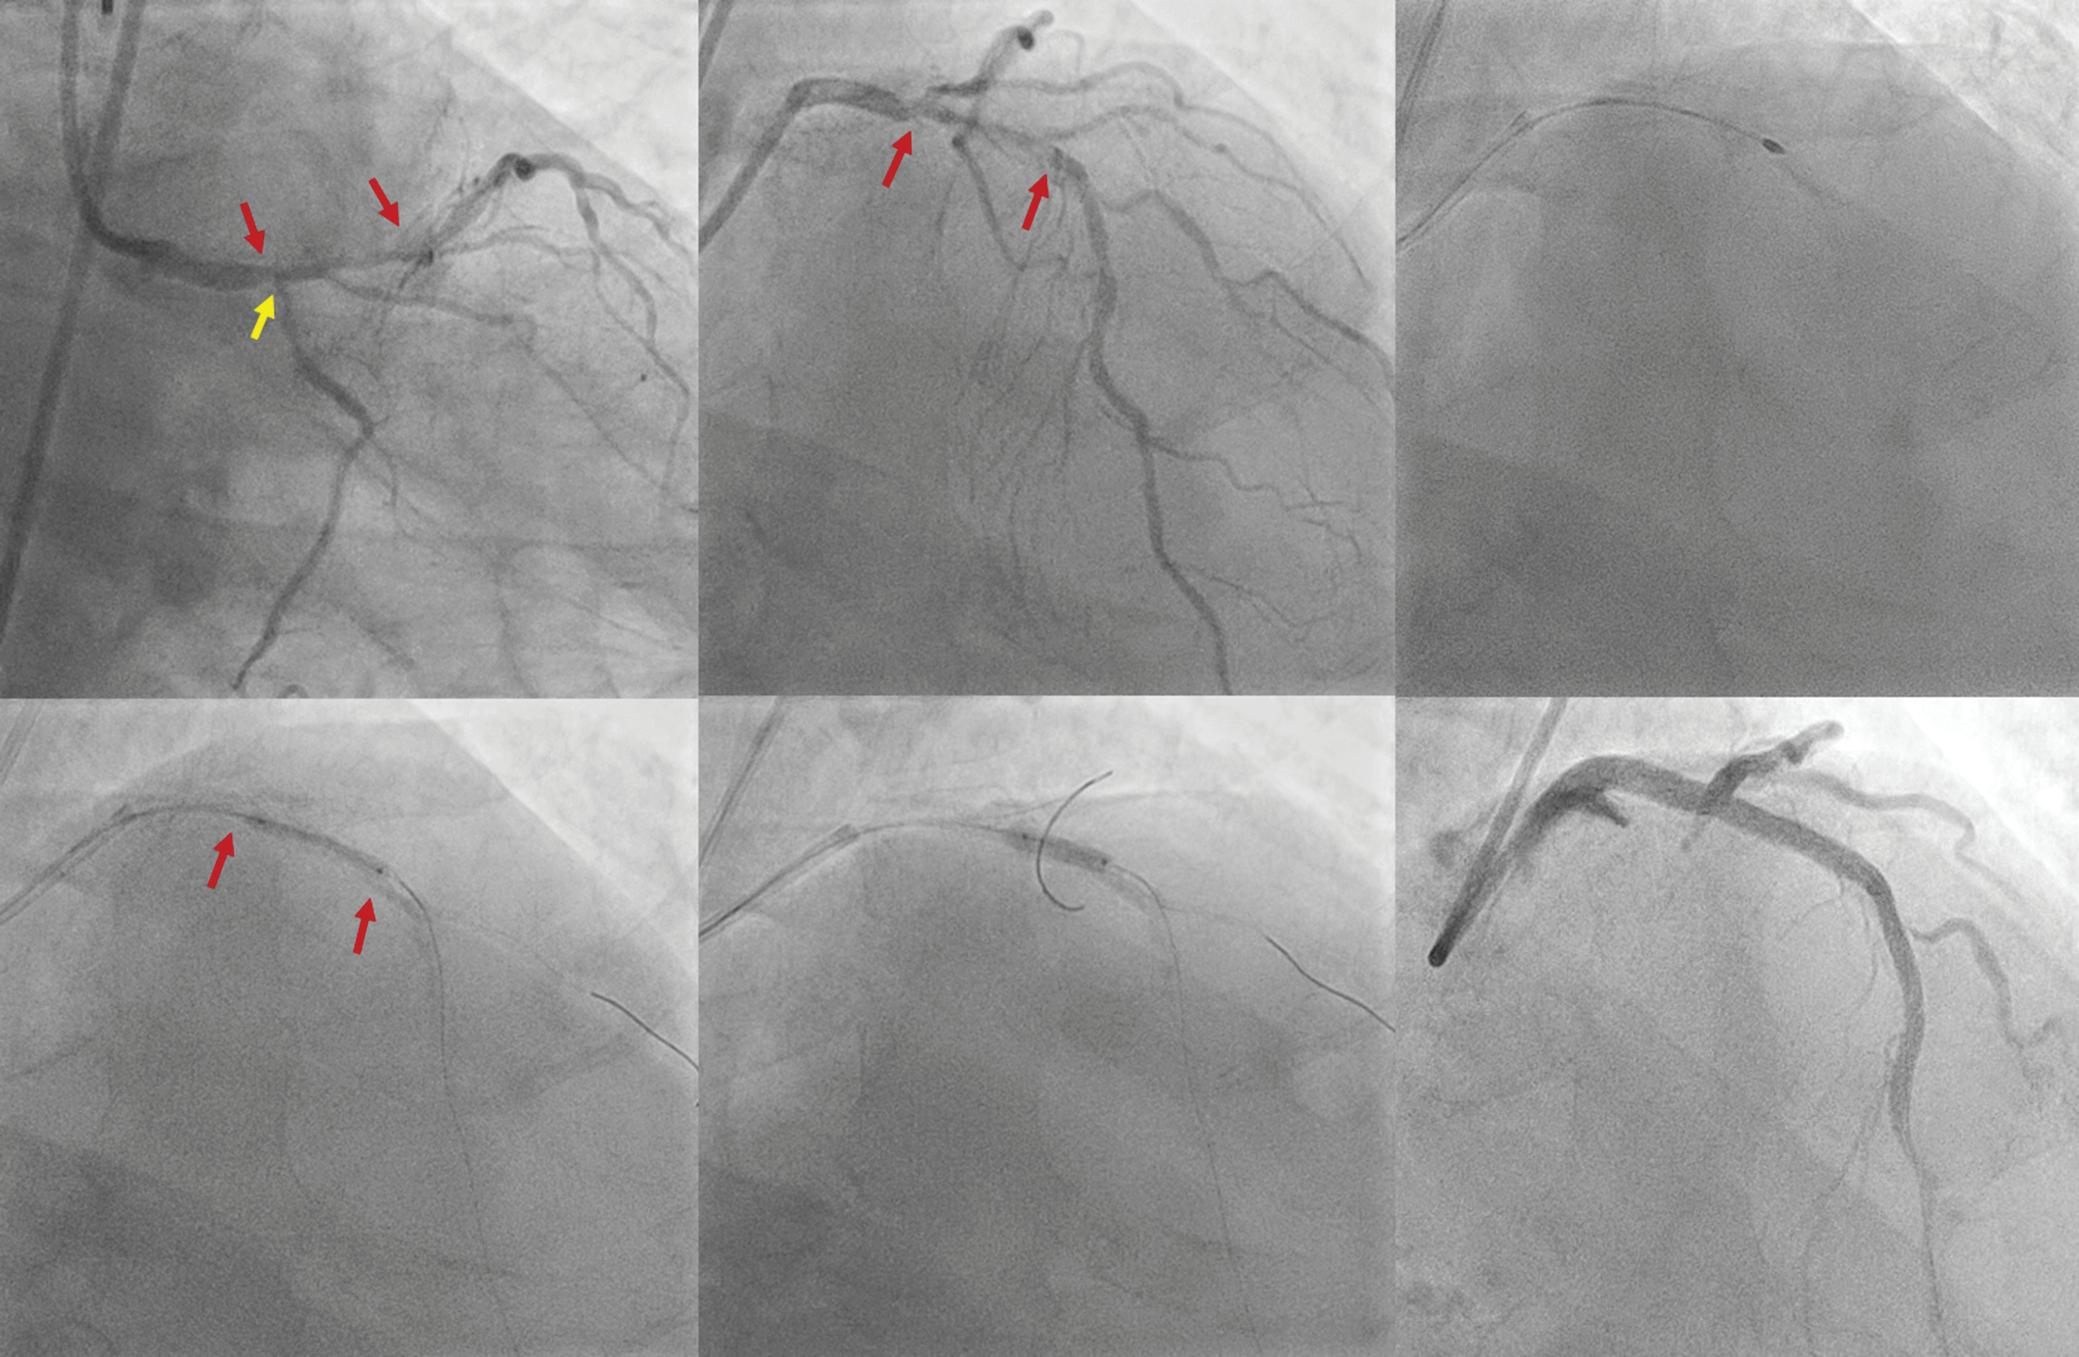

7. Smedema JP, Van Kroonenburgh MJ, Snoep G, et al. Cardiac sarcoidosis in a patient with hypertrophic cardiomyopathy demonstrated by magnetic resonance imaging and single photon emission computed tomography dual-isotope scintigraphy. Circulation 2004;110:e529–31.

https://doi.org/10.1161/01.CIR.0000149749.95902.A4; PMID: 15596554.

Cardiac Sarcoidosis, Pericardial Effusion and Stress-induced Cardiomyopathy JOURNAL OF ASIAN PACIFIC SOCIETY OF CARDIOLOGY www.JAPSCjournal.com

European Examination in Core Cardiology (APSC Exit Examination)

Jack WC Tan,1,2,3 Jonathan Yap,1,2 Khung Keong Yeo,1,2 Derek P Chew,4 Alan Yean Yip Fong,5,6 Caitlyn Tan,7 Abdul Shehab,8 Nguyen Ngoc Quang,9 Terrence Chua,1 Clive Lawson,10 Danny Mathysen,11,12 Stephanie Thibault,13 Wael Al Mahmeed14 and Chris Plummer15

1. Department of Cardiology, National Heart Centre Singapore; 2. Duke-NUS Medical School, Singapore; 3. Department of Cardiology, Sengkang General Hospital, Singapore; 4. Department of Cardiology, Flinders University College of Medicine and Public Health, Adelaide, Australia; 5. Department of Cardiology, Sarawak Heart Centre, Kota Samarahan, Sarawak, Malaysia; 6. Faculty of Medicine and Health Sciences, University Malaysia Sarawak, Kota Samarahan, Sarawak, Malaysia; 7. National University of Singapore Yong Loo Lin School of Medicine, Singapore; 8. College of Medicine and Health Sciences, UAE University, Al Ain, United Arab Emirates; 9. Department of Cardiology, Hanoi Medical University, Hanoi, Vietnam; 10. Department of Cardiology, Maidstone and Tunbridge Wells NHS Trust, Maidstone, UK; 11. Department of Ophthalmology, Antwerp University Hospital, Edegem, Belgium; 12. Faculty of Medicine and Health Sciences, University of Antwerp, Wilrijk (Antwerp), Belgium; 13. European Society of Cardiology (ESC), Biot, France; 14. Heart and Vascular Institute, Cleveland Clinic, Abu Dhabi, United Arab Emirates; 15. Department of Cardiology, Freeman Hospital, The Newcastle upon Tyne Hospitals NHS Foundation Trust, Newcastle upon Tyne, UK

Keywords

European Examination in Core Cardiology (EECC), Asian Pacific Society of Cardiology (APSC), Asia–Pacific, exit examination, core cardiology

Disclosure: JWCT is on the Editorial Board of the Journal of Asian Pacific Society of Cardiology; this did not influence peer review. JWCT has received honoraria from AstraZeneca, Bayer, Amgen, Medtronic, Abbott Vascular, Biosensors, Alvimedica, Boehringer Ingelheim and Pfizer; research and educational grants from Medtronic, Biosensors, Biotronik, Philips, Amgen, AstraZeneca, Roche, Otsuka, Terumo and Abbott Vascular; and consulting fees from Elixir, CSL Behring and Radcliffe Publishing. JY is an Associate Editor of the Journal of Asian Pacific Society of Cardiology; this did not influence peer review. KKY is Editor-in-Chief of the Journal of Asian Pacific Society of Cardiology; this did not influence peer review. KKY has received institutional research funding from Medtronic, Boston Scientific, Amgen, AstraZeneca and Shockwave Medical; consulting or honoraria fees from Medtronic, Boston Scientific, Abbott Vascular, Amgen, Bayer and Novartis; and speaker or proctor fees from Abbott Vascular, Boston Scientific, Medtronic, Philips, Shockwave Medical, Alvimedica, Menarini, AstraZeneca, Amgen and Bayer. DPC is a Deputy Editor of the Journal of Asian Pacific Society of Cardiology; this did not influence peer review. DPC has received consulting fees from the Asian Pacific Society of Cardiology (APSC); support for travel to meetings for the study or otherwise from the APSC; grants/grants pending from Roche Diagnostics and AstraZeneca; and payment for the development of educational presentations, including service on speakers’ bureaus, from AstraZeneca AYYF is an Associate Editor and NNQ and WAM are on the Editorial Board of the Journal of Asian Pacific Society of Cardiology; this did not influence peer review. All other authors have no conflicts of interest to declare.

Acknowledgements: The authors thank Ivan Olegario for medical writing support.

Received: 5 April 2022 Accepted: 7 June 2022 Citation: Journal of Asian Pacific Society of Cardiology 2022;1:e24. DOI: https://doi.org/10.15420/japsc.2022.15

Correspondence: Jack Wei Chieh Tan, Department of Cardiology, National Heart Centre, 5 Hospital Drive, Singapore 169609. E: jack.tan.w.c@singhealth.com.sg

Open Access: This work is open access under the CC-BY-NC 4.0 License which allows users to copy, redistribute and make derivative works for non-commercial purposes, provided the original work is cited correctly.

The European Examination in Core Cardiology (EECC), known as the European Examination in General Cardiology prior to 2020, is a joint venture between the European Society of Cardiology (ESC), the Union of European Medical Specialists Cardiology Section and participating national cardiac societies. The EECC is also supported by independent academic oversight.1

In 2012, the ESC launched the first pilot examination with 80 volunteers from Ireland, the Netherlands, Portugal, Spain and UK; since 2013, there have been annual sittings of the European Examination in General Cardiology/ EECC with the participation of the ESC National Cardiac Societies network.

The purpose of the examination is to provide a broad, balanced and upto-date test of the core knowledge required by cardiology specialty trainees for independent practice.1

The examination assesses knowledge from current evidence-based guidelines and published research, and has recently been aligned with

the ESC Core Curriculum for the Cardiologist, published in 2020.2 The examination is intended to complement workplace-based assessments as part of a comprehensive cardiology training programme, as well as to facilitate progressive improvement and harmonisation of cardiology training and clinical practice.1 Participating cardiac national societies use the EECC in different ways to support the medical education of cardiology trainees in their country. Trainees are advised to take the EECC once they have completed core training, so that unsuccessful candidates may have the opportunity to re-sit the examination before the end of their overall training.1

The Asian Pacific Society of Cardiology (APSC) is an umbrella organisation representing 22 cardiology societies in the Asia–Pacific region.3 Due to the heterogeneity of the region, the completion of cardiology training and entry into continuous professional development varies across the region. There is no uniform cardiology subspecialty training, and no uniform exit examination to assess the core cardiology knowledge of trainees.

General Cardiology EDITORIAL © 2022 The Author(s). Published by Radcliffe Group Ltd. www.JAPSCjournal.com

In 2020, the APSC approached the ESC to pilot the EECC, and to determine how the APSC could participate and support the deployment of the examination and its administration in the region for cardiac societies that are part of the APSC but may not be able to join the EECC on their own. Examinees from member countries of the APSC are nominated to take the same EECC examination as their Western counterparts. The examinees are advised to take the examination anytime within 6 months before to 6 months after their own country’s general cardiology exit examination.

In this article we describe the development and administration of the pilot EECC (APSC Exit Examination). The examination results of the APSC examinees over the first 3 years of implementation will be published in a future paper. This analysis is intended to benchmark the knowledge of cardiology trainees as part of the evaluation of the quality of training in the region and to guide future plans for the improvement and harmonisation of cardiology training.

Methodology

Examination Development

Every year, the writing of the EECC (APSC Exit Examination) starts with question writing meetings in August of the preceding year (August 2019 for the first pilot examination) and the following January (Figure 1). The examination questions are written and edited by groups of cardiologists representing their national cardiology societies and the APSC, all of whom come from all subspecialties within cardiology. The examination questions test knowledge that is mapped to the ESC core curriculum, in line with current guidelines and published clinical studies. The questions cover the following four sections:

• imaging and valvular heart disease;

• rhythm disorders;

• coronary artery disease, acute cardiovascular care, prevention, rehabilitation and sports; and